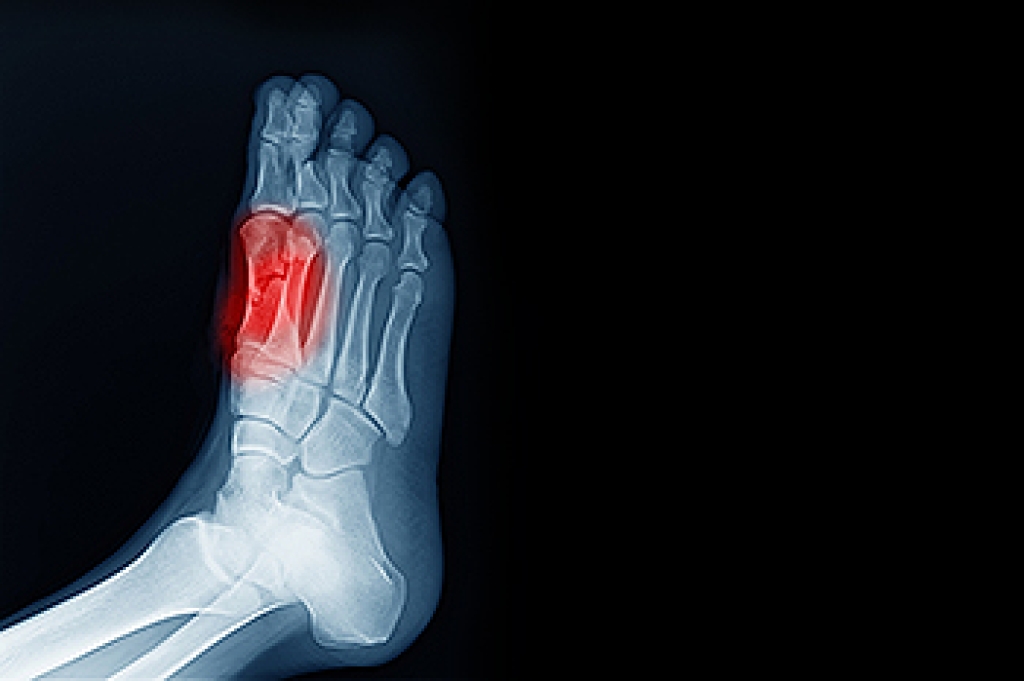

Diabetic foot problems pose significant challenges to an individual's quality of life due to their potential for severe complications. Diabetes can lead to neuropathy, reduced blood flow, and impaired wound healing, increasing the risk of foot ulcers, infections, and even amputations. These conditions often cause chronic pain, limited mobility, and decreased independence, impacting daily activities and overall well-being. Furthermore, managing diabetic foot problems requires rigorous self-care routines, frequent medical appointments, and lifestyle adjustments, which can be physically and emotionally demanding. The fear of potential complications and the burden of constant vigilance over foot health can contribute to anxiety, depression, and decreased social participation. Effective management strategies, including proper foot care, regular monitoring, and early intervention for any issues, are essential for preserving mobility and minimizing the impact of diabetic foot problems on quality of life. If you have diabetes and it has impacted your feet, it is strongly suggested that you are under the care of a podiatrist for routine visits, in addition to receiving prompt treatment as needed.

Diabetes affects millions of people every year. The condition can damage blood vessels in many parts of the body, especially the feet. Because of this, taking care of your feet is essential if you have diabetes, and having a podiatrist help monitor your foot health is highly recommended.